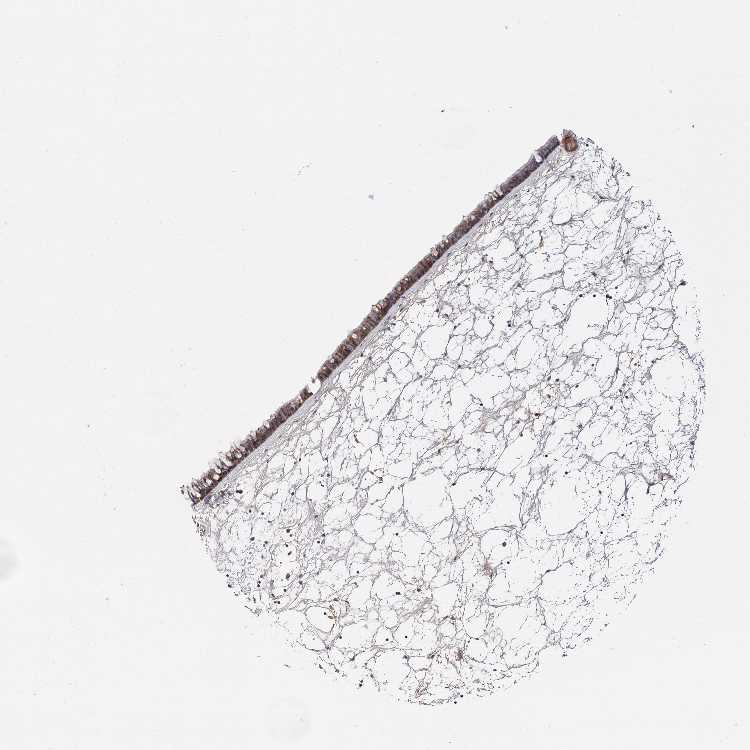

SNX15